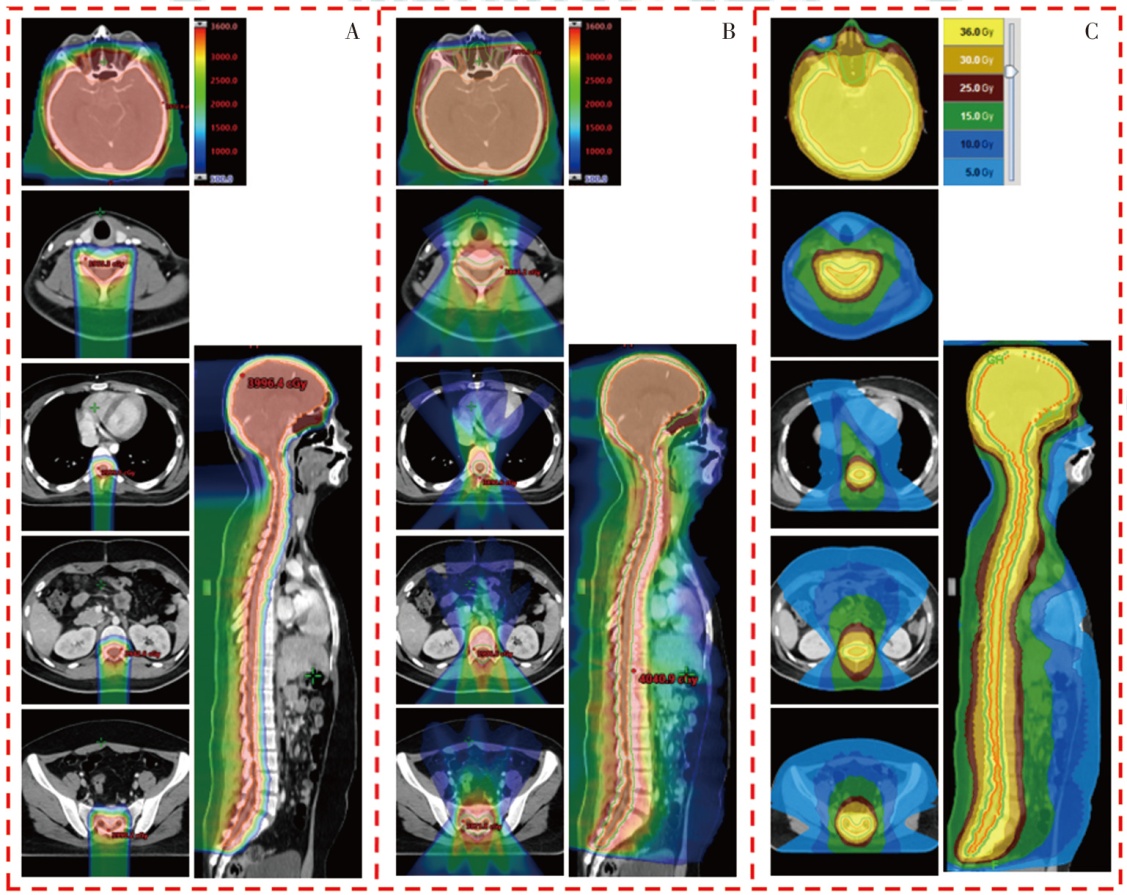

目的 探索质子调强放疗(IMPT)、光子固定野调强放疗(IMRT)以及光子螺旋断层放疗(TOMO)技术应用于儿童全中枢神经系统肿瘤照射的剂量学特点。方法 以1例山东省肿瘤防治研究院(山东省肿瘤医院)临床诊断为非典型畸胎样/横纹肌样瘤、脊膜转移、脑膜转移,行全脑全脊髓放疗(CSI)的14岁儿童患者靶区为例,根据靶区的临床处方和危及器官(OAR)的限值要求,分别设计IMPT、IMRT和TOMO计划。对各计划靶区的适形指数(CI)、均匀性指数(HI)和梯度指数(GI),以及正常组织的剂量体积指标进行评估,对比3类计划的剂量学特点。结果 IMPT计划的CI(0.71)、HI(0.05)和GI(3.13)均与IMRT计划(0.80、0.08、3.14)相当,TOMO计划的HI(0.03)、GI(2.54)较优,且均在临床接受范围内。IMPT计划中并行器官受照剂量低于IMRT和TOMO计划;IMPT计划中双肺V5为2.9%,IMRT为37.6%,TOMO为43.5%;IMPT计划的肝脏Dmean为0.01 Gy(RBE),IMRT计划为6.12 Gy,TOMO计划为6.39 Gy;IMPT计划中膀胱、直肠、股骨头均没有受量,而在IMRT和TOMO计划中均有低剂量辐射。对于毗邻靶区和包含在靶区内的串行器官,IMPT计划中脊髓和脑干的Dmax分别为39.89和39.88 Gy(RBE),IMRT计划分别为39.43 和38.59 Gy,TOMO计划分别为38.41和37.69 Gy。IMPT计划中低剂量区显著优于光子放疗计划,其中患者体内10%的处方剂量区域所占的绝对体积IMPT计划较IMRT计划减少了70.10%,较TOMO计划减少了76.96%;30%的处方剂量体积IMPT计划较IMRT计划减少了53.49%,较TOMO计划减少了62.51%;50%的处方剂量体积IMPT计划较IMRT计划减少了39.06%,较TOMO计划减少了42.23%。结论 在儿童CSI中,IMPT计划的低剂量区与并行OAR受照剂量显著少于IMRT和TOMO计划。3种计划的CI、HI和GI均能满足临床要求。对于毗邻靶区和包含在靶区内的串行器官,IMPT计划的Dmax可能比IMRT和TOMO计划剂量更高。

Objective To explore the dosimetric characteristics of intensity modulated proton therapy (IMPT),intensity modulated radiation therapy (IMRT) and tomotherapy (TOMO) techniques applied in the irradiation of pediatric whole central nervous system tumors. Methods Taking the target area of a 14-year-old pediatric patient clinically diagnosed with atypical teratoid/rhabdomyoid tumor,meningeal metastasis by Shandong Cancer Hospital and Institute,and undergoing craniospinal irradiation (CSI) as an example,IMPT,IMRT and TOMO plans were designed respectively based on the clinical prescription of the target area and the limit requirements of organs at risk (OARs). The conformal index (CI),homogeneity index (HI) and gradient index (GI) of each planning target volume,as well as the dose volume index of normal tissues,were evaluated to compare the dosimetric characteristics of the three types of plans. Results The CI (0.71),HI (0.05) and GI (3.13) of the IMPT plan were comparable to those of IMRT plan (0.80,0.08,3.14). The HI (0.03) and GI (2.54) of the TOMO plan were excellent,which were all within the clinically acceptable range. The irradiation dose to parallel organs in the IMPT plan was lower than that in the IMRT and TOMO plan. In the IMPT plan,V5 of lungs was 2.9%,IMRT plan was 37.6%,and TOMO plan was 43.5%. The Dmean of liver in the IMPT plan was 0.01 Gy(RBE),IMRT plan was 6.12 Gy,and TOMO plan was 6.39 Gy. In the IMPT plan,none of the bladder,rectum,and femoral head received the dose,while there was low-dose radiation in both IMRT and TOMO plan. For serial organs adjacent to and within the target area,the Dmax of spinal cord and brainstem in IMPT plan was 39.89 and 39.88 Gy(RBE),respectively; in IMRT plan,they were 39.43 and 38.59 Gy,respectively; and in TOMO plan,they were 38.41 and 37.69 Gy,respectively. The low-dose area in the IMPT plan was significantly better than the photon radiotherapy plans. Among them,the absolute volume IMPT plan occupied by 10% of the prescribed dose area in the patient's body was reduced by 70.10% compared with IMRT plan and 76.96% compared with TOMO plan; the 30% prescribed dose volume IMPT plan was reduced by 53.49% compared with IMRT plan and 62.51% compared with TOMO plan; the 50% prescribed dose volume IMPT plan was reduced by 39.06% compared with IMRT plan and 42.23% compared with TOMO plan. Conclusions The IMPT plan demonstrated significantly reduced low-dose exposure and lower doses to parallel OARs compared to both IMRT and TOMO plans in pediatric CSI. The CI,HI and GI of the three plans can all meet the clinical requirements. However,for serial organs adjacent to and within the target area,the Dmax of the IMPT plan may be higher than that of IMRT and TOMO plans.